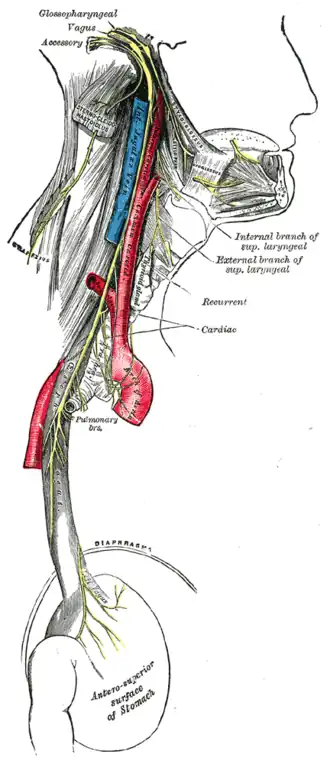

Course and distribution of the glossopharyngeal, vagus, and accessory nerves. | |

Upon leaving the medulla oblongata between the olive and the inferior cerebellar peduncle, the vagus nerve extends through the jugular foramen, then passes into the carotid sheath between the internal carotid artery and the internal jugular vein down to the neck, chest, and abdomen, where it contributes to the innervation of the viscera, reaching all the way to the colon. Besides giving some output to various organs, the vagus nerve comprises between 80% and 90% of afferent nerve fibers conveying sensory information about the state of the body's organs to the central nervous system.[4]

The right and left vagus nerves descend from the cranial vault through the jugular foramina,[5] penetrating the carotid sheath between the internal and external carotid arteries, then passing posterolateral to the common carotid artery. The cell bodies of visceral afferent fibers of the vagus nerve are located bilaterally in the inferior ganglion of the vagus nerve (nodose ganglia).The vagus runs parallel to the common carotid artery and internal jugular vein inside the carotid sheath.

Right Vagus Nerve: The right vagus nerve gives rise to the right recurrent laryngeal nerve, which hooks around the right subclavian artery and ascends into the neck between the trachea and esophagus. The right vagus then crosses anterior to the right subclavian artery, runs posterior to the superior vena cava, descends posterior to the right main bronchus, and contributes to cardiac, pulmonary, and esophageal plexuses. It forms the posterior vagal trunk at the lower part of the esophagus and passes through the diaphragm to enter the abdomen through the esophageal hiatus.

Left Vagus Nerve: The left vagus nerve enters the thorax between left common carotid artery and left subclavian artery and descends on the aortic arch. It gives rise to the left recurrent laryngeal nerve, which hooks around the aortic arch to the left of the ligamentum arteriosum and ascends between the trachea and esophagus. The left vagus further gives off thoracic cardiac branches, breaks up into the pulmonary plexus, continues into the esophageal plexus, and enters the abdomen as the anterior vagal trunk by way of the esophageal hiatus of the diaphragm.